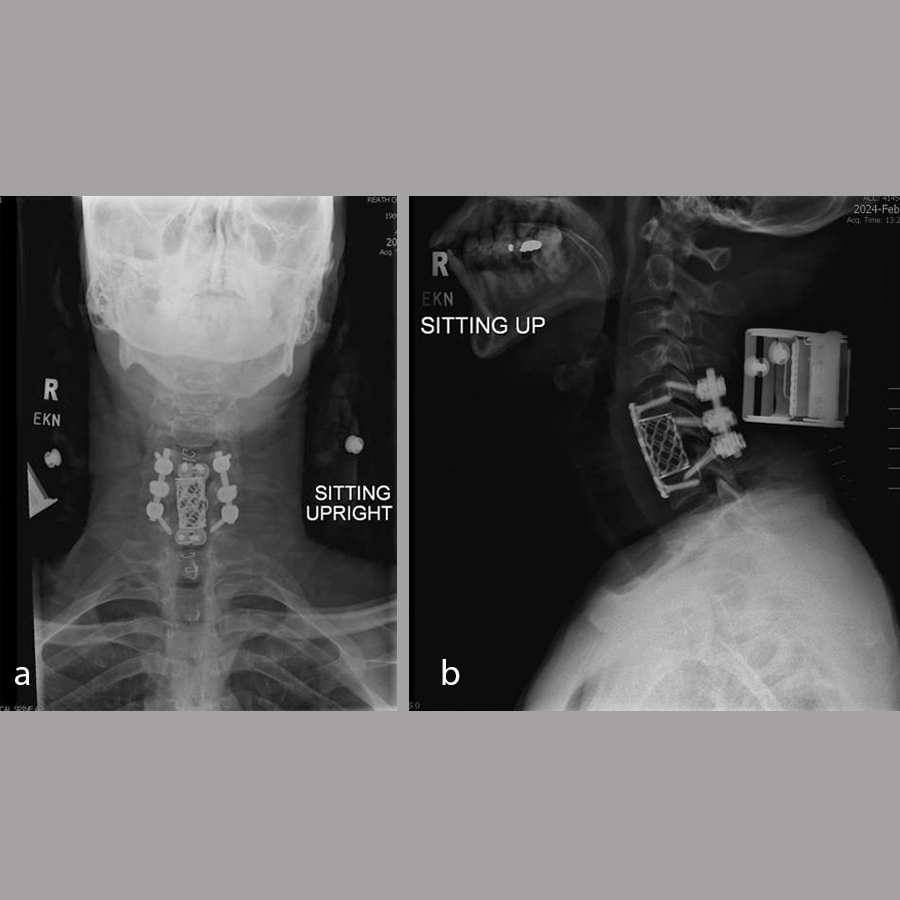

The patient underwent a C6 corpectomy with removal of fractured C6 vertebral body, restoration of height and placement of a Synmesh cage filled with autograft from the fracture. Following restoration of height and vertebral body reconstruction, a CODA™ ACP plate was applied anteriorly with screws into the C5 and C7 vertebral bodies. Given the psychosocial nature of the patient and the fracture pattern, the patient was then placed prone and underwent posterior instrumentation with Symphony instrumentation with lateral mass screws into C5 and C6 bilaterally and pedicle screws into C7 followed by placement of 4 mm rods along with fusion (Fig 11). The patient did well postsurgery (Fig 12) and was discharged according to protocol, but was unfortunately then lost to follow-up.